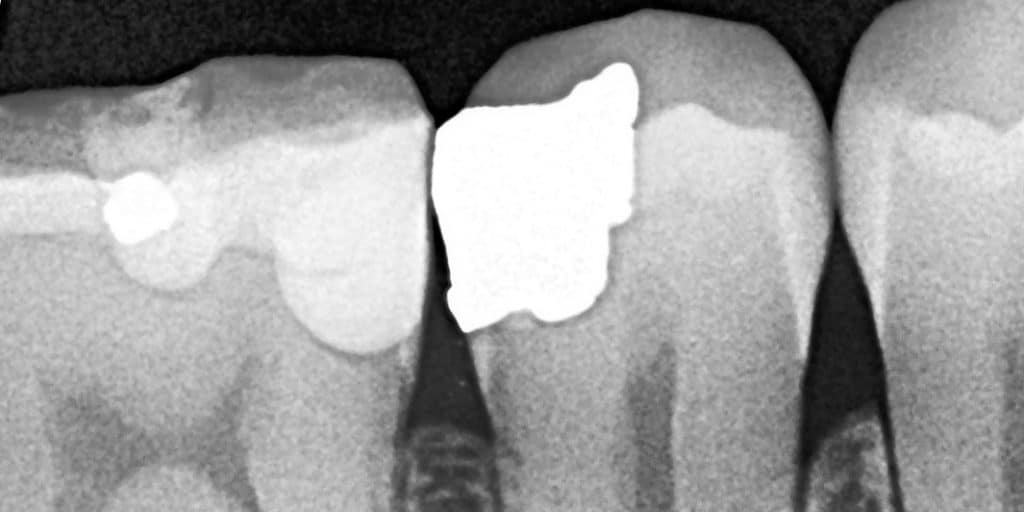

X Ray .... After